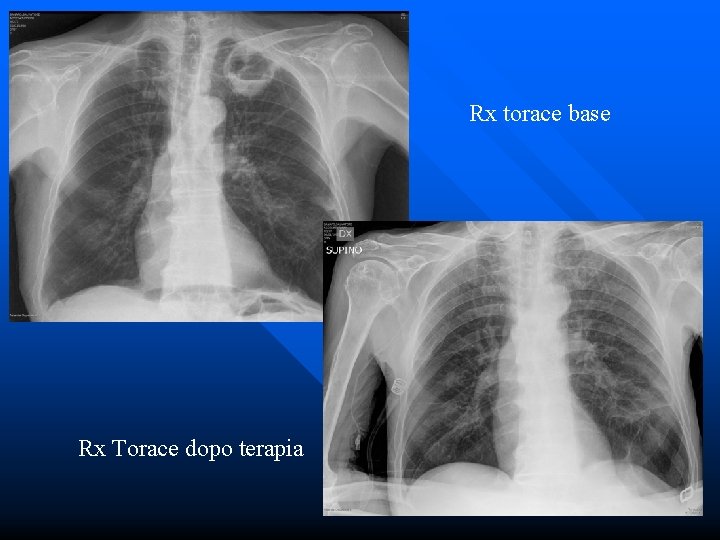

Rx torace base Rx Torace dopo terapia